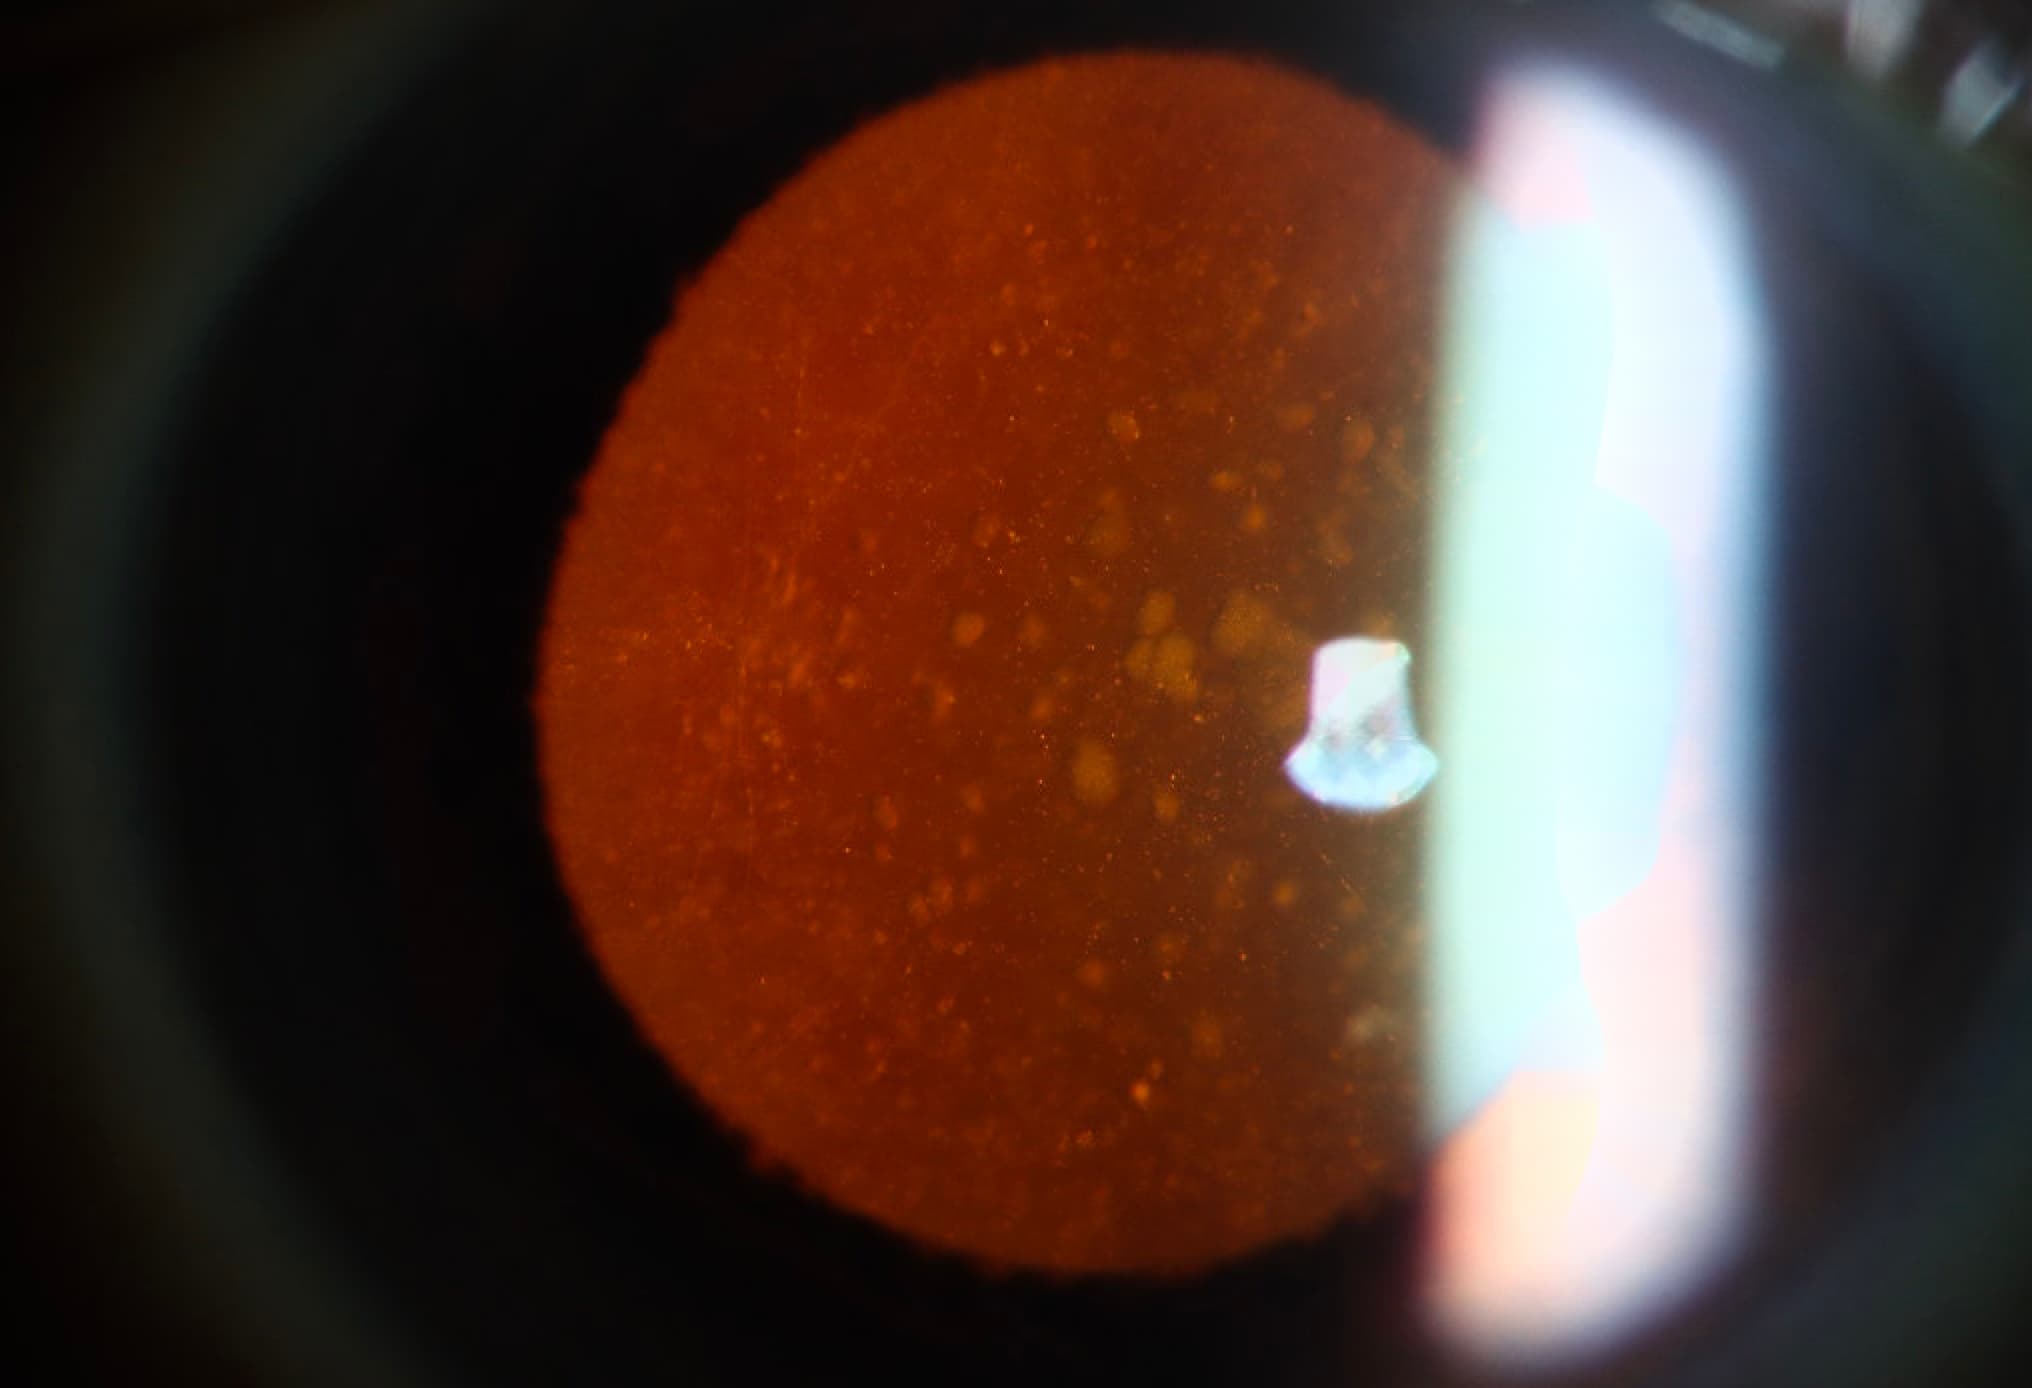

Clinical Images

High-resolution clinical photographs showing various presentations of anisocoria (unequal pupils).